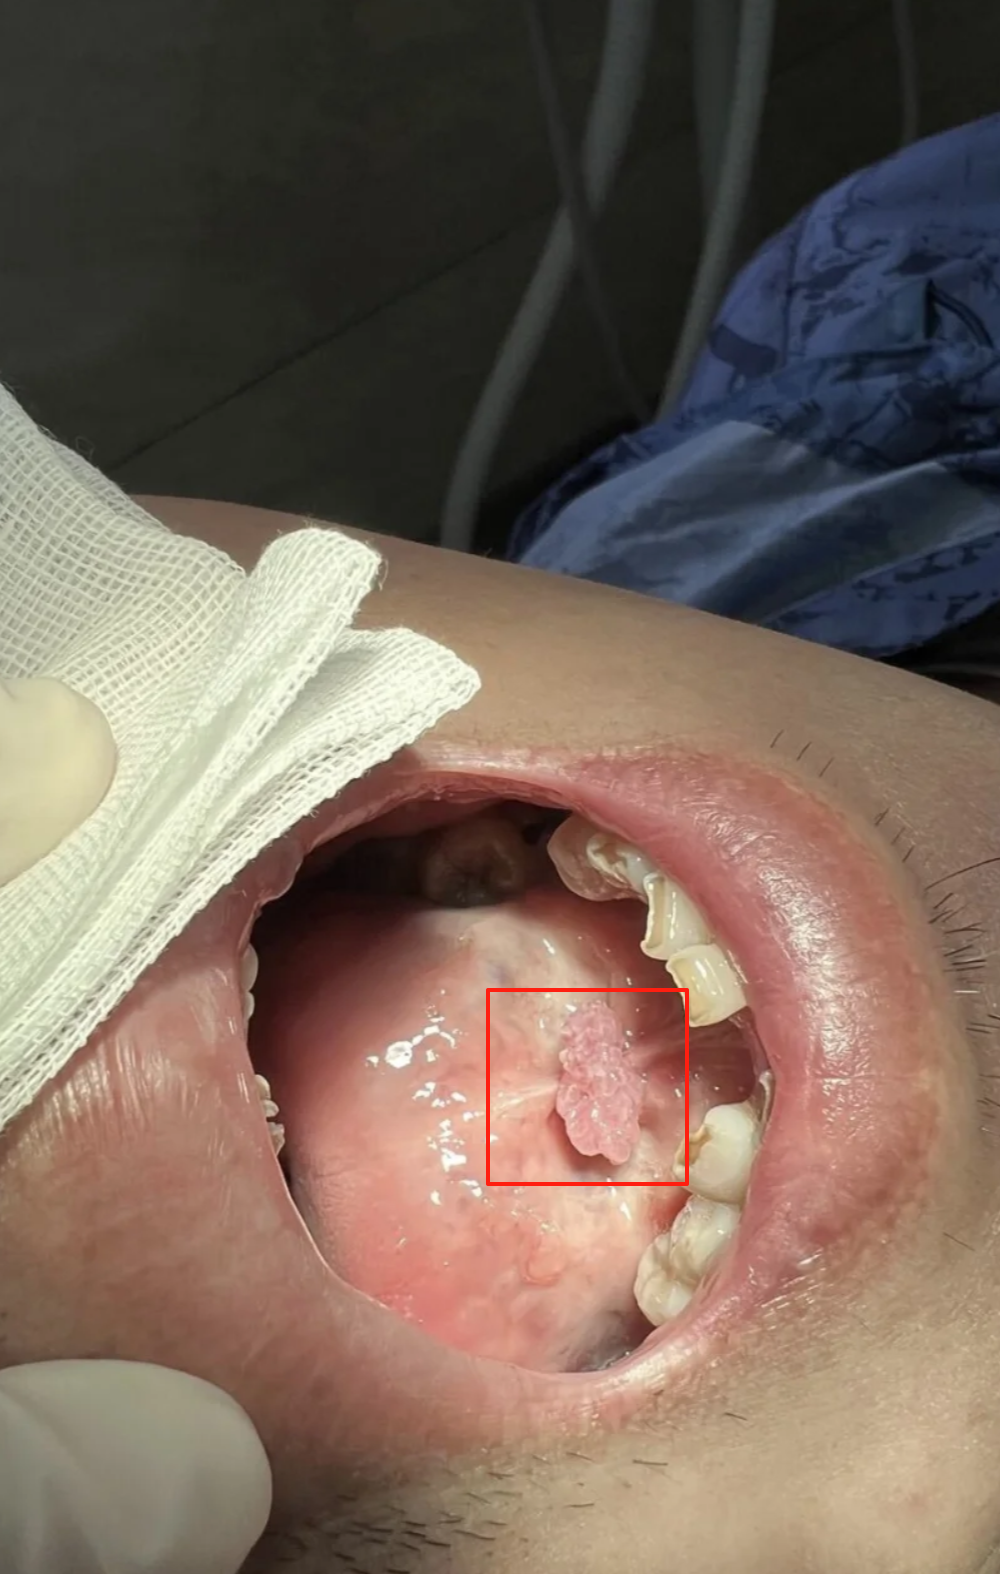

男性口腔尖锐湿疣症状图片

口腔尖锐湿疣9